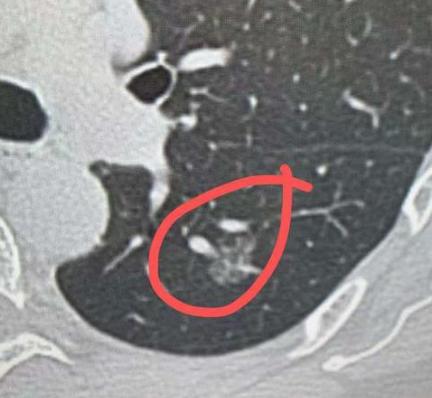

肺磨玻璃结节有血管穿过,癌细胞会全身扩散?平时在门诊,经常碰到很多朋友带着肺结节的报告来找我,一个个都特别紧张,最常问的就是:医生,我这个磨玻璃结节,报告上说有血管穿过,是不是里面的癌细胞,会顺着血管跑到全身去? 其实大家完全不用这么担心,这种顾虑真的没必要。 尤其是咱们说的小结节,特别是磨玻璃性质的小结节,情况真的没那么糟糕。很多人觉得,只要有血管穿过结节,癌细胞就一定会进入血液扩散,其实不是这样的,癌细胞能不能进入血液、扩散到全身,不是单看这一个情况就能决定的。 咱们重点说下磨玻璃小结节,这种结节里的细胞,大多是贴在肺泡壁上生长的,还没有突破基底膜——简单说就是,这些细胞还被一层屏障挡着,根本没办法轻易跑到血管里去。 再说说大家关心的“血管穿过”,其实很多时候,就是血管刚好长在了结节的中间或者穿行而过,这只是结节的一种形态表现而已。 我们医生看报告、判断结节是良性还是恶性的时候,会把这个作为一个参考依据,但这绝对不代表,只要有血管穿过,就一定有危险,更不意味着癌细胞已经进入血管了。 所以我特别想跟大家说,面对“血管穿过肺磨玻璃结节”这个情况,一定要理性看待,别一听到这几个字就慌了神、瞎琢磨。 碰到肺结节不可怕,保持平常心,严格听专业医生的建议,定期过来复查、随访,这才是最稳妥、最明智的做法。[作揖][玫瑰]